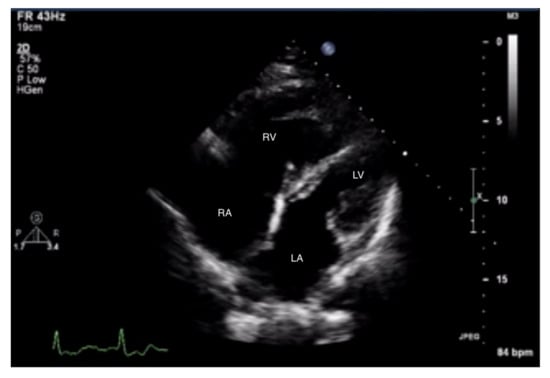

Figure 1.

Enlarged right ventricle. Two-dimensional transthoracic echocardiography (2D-TTE), parasternal long-axis view (PLAX). RV: right ventricle, LV: left ventricle, LA: left atrium.

Figure 2.

Enlarged right ventricle. 2D-TTE, parasternal short-axis view (PSAX). RV: right ventricle, LV: left ventricle.

When pulmonary circulation pressure increases in the course of PAH, the right ventricle (RV) is subjected to overload. Initially, it adapts to an increased vascular load by increasing muscle contraction force by up to 5-fold, thus maintaining normal stroke volume values. To maintain the increased contractility, the right ventricular muscle mass increases [10], and wall hypertrophy and RV cavity dilatation occur [11]. Thus, in the course of PAH, there are changes in the size ratio between the two ventricles. In advanced stages, the right ventricle is larger than the left (Figure 1 and Figure 2). Statistically, in patients with PAH, the RV is more dilated and functions worse than in other diseases characterized by pulmonary hypertension [12].

Measurements of both ventricles are recommended in the four-chamber (4CH) view, and the correct projection during measurements should be maintained (Figure 3 and Figure 4). In assessing the linear dimension of the right ventricle, the goal should be to obtain the maximum dimension of the right ventricle while preserving the visibility of the apex and the plane of section passing through the center of the LV. RV measurement in a five-chamber view with a visible left ventricular outflow tract is erroneous [13]. Under these measurement conditions, the normal RV size should not exceed 2/3 of the LV dimension [14].